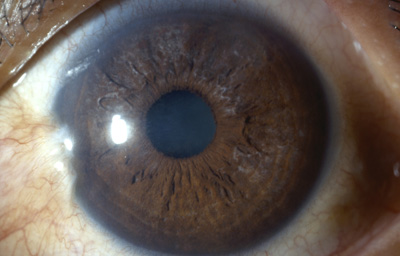

Caso No21.

Paciente 25 años, estudiante ( Barranquilla); Desea control ya que hace 15 años picadura de abeja “africana”en el Ojo Izquierdo.

Al examen: Nubécula adelgazada “con aguijón desnaturalizado en córnea”; córnea sin edema con buena trasparencia y cámara anterior media. Iris con pupila negra, central y redonda con sinequia anterior de hoja anterior del Iris de 5 a 8 en periferia e Iridoschisis, sin pérdida de pigmento en el Iris . Cristalino trasparente, polo posterior bien. TO: 17 en ambos ojos aplanático de Goldman. (Fotos 26 y 27)

Se entrega nueva fórmula de anteojos.

Foto 26 - Leucoma a las 2 con agujón “in situ

Foto 27 - Aguijón desnaturalizado